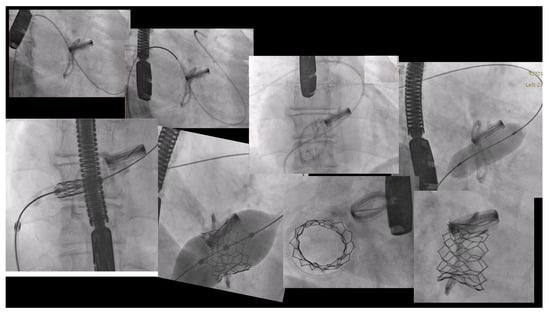

6.1. Procedure